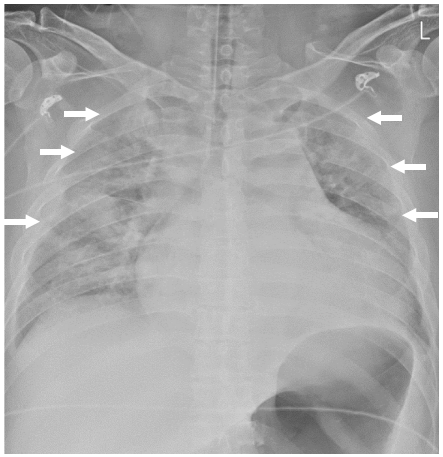

患者男,38岁,吸烟,有不明原因的心律失常史,无治疗,因右侧偏瘫入院。在初次检查时,患者处于昏迷状态,格拉斯哥昏迷评分为7分。患者被诊断为左大脑中动脉(MCA)区域梗死(图1A),左大脑中动脉M1段闭塞(图1B)。有房颤、心力衰竭伴左心室射血分数(LVEF) 27%(表1)、肺水肿、胸腔积液和轻度心脏扩大(图2)。

图2: 胸部x线显示肺水肿,胸腔积液,和轻微的心脏扩大(箭头)